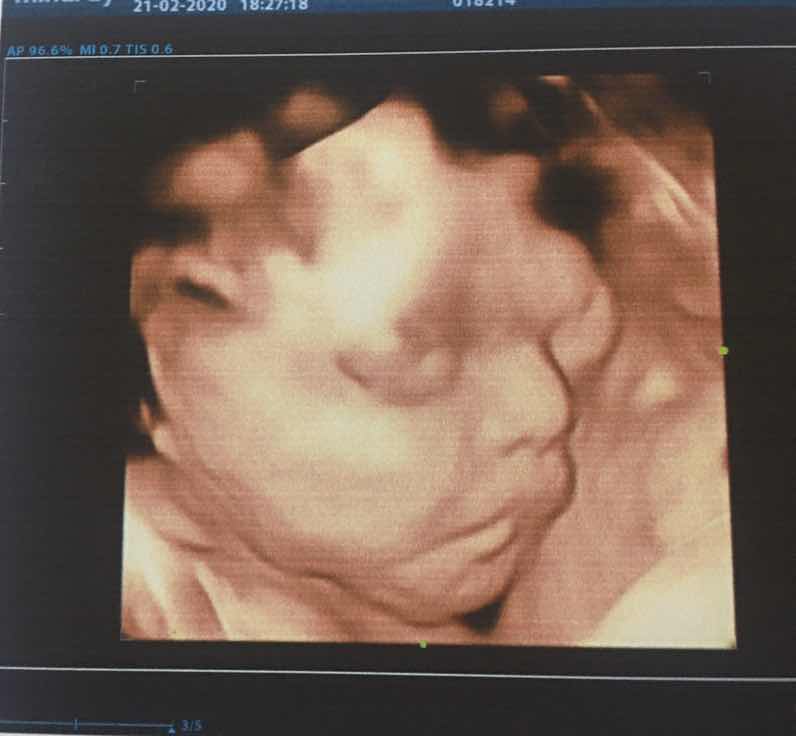

ขอดูรูปอัลตราซาวด์4มิติของเพื่อนๆหน่อยค่ะ 25week

23wค่ะบ้านนี้ลูกสาว